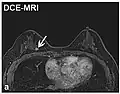

| Dynamic contrast enhanced | DCE | Measures changes over time in the shortening of the spin–lattice relaxation (T1) induced by a gadolinium contrast bolus.[90] | Faster Gd contrast uptake along with other features is suggestive of malignancy (pictured).[91] |

| |